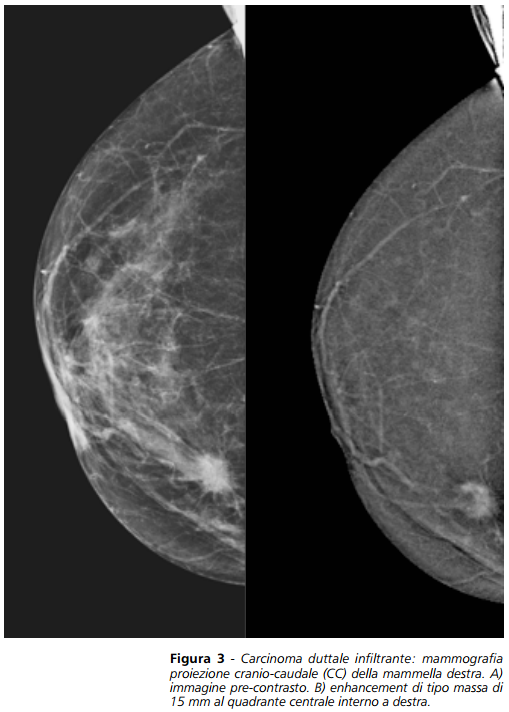

La CESM consiste nell’acquisizione di mammografie digitali a bassa ed alta energia con tecnica Dual Energy dopo la somministrazione di mezzo di contrasto (mdc) iodato endovena, con successiva sottrazione spettrale e produzione di una immagine mammografica combinata, ove si evidenzia solo il mdc e che permette di ridurre il rumore anatomico (Figura 1). La CESM è una tecnica recente e promettente nel management del tumore mammario; è un esame affidabile che ha mostrato una accuratezza diagnostica elevata nella diagnosi di lesioni maligne, comparabile alla RM e maggiore della mammografia convenzionale; I vantaggi maggiori sono il basso costo, la facilità di installazione, la buona tolleranza e confort, e la maggiore facilità di lettura rispetto alla mammografia standard.Per eseguire l’esame, la paziente deve presentarsi a digiuno, avere eseguito un esame del sangue che confermi che la creatininemia sia nella norma ed aver eseguito una preparazione farmacologica in caso di diatesi allergica. Viene quindi posizionato un accesso venoso e somministrato il mdc iodato, con dose di circa 1,5ml/kg con iniettore automatico per assicurare un flusso costante. Dopo 2 minuti dalla somministrazione del mdc si acquisiscono una serie di immagini a bassa ed alta energia in rapida successione mentre la mammella rimane compressa per i pochi secondi necessari per l’esecuzione dell’esame. Vengono eseguite le 4 proiezioni standard (CC, OBL) bilateralmente. (Figura 2). L’esame ha una durata complessiva inferiore a 10 minuti ed è ben tollerato dalle pazienti. Per quanto riguarda la dose per la CESM, è solo lievemente aumentata rispetto alla classica mammografia. L’esposizione a bassa energia corrisponde a una mammografia convenzionale, mentre per l’esposizione ad alta energia si può stimare che l’esposizione corrisponda a circa il 20% di una mammografia convenzionale; quindi complessivamente la dose alla paziente è circa 1.2-1.5 volte quella di una mammografia convenzionale. Dal 2003 ad oggi sono stati condotti 10 studi con CESM che hanno arruolato 942 pazienti ove la CESM ha mostrato una sensibilità media del 94% e specificità del 81%. Presso l’Istituto di Ricerche Cliniche Fanfani sono stati eseguiti 13 esami di CESM da Dicembre 2014 ad Aprile 2015 (77% per stadiazione e 23% per problem solving), e la metodica ha mostrato una sensibilità del 100% con VPN del 100%, dimostrandosi accurata nel corretto

inquadramento per il successivo iter diagnostico terapeutico e nella valutazione dimensionale della lesione in fase preoperatoria. Il mammografo utilizzato è stato il Selenia Dimensions di Hologic Inc. (Bedford, MA, USA). Alla luce degli studi presenti in letteratura e dell’esperienza personale è possibile affermare che l’esame CESM sia un esame affidabile che ha mostrato una accuratezza diagnostica elevata nella diagnosi di lesioni maligne, comparabile alla RM e maggiore della mammografia convenzionale; permette di aumentare la sensibilità diagnostica della mammografia senza perderne specificità, ha infatti un alto valore predittivo positivo. Permette inoltre di incrementare il valore predittivo negativo con una forte riduzione dei falsi negativi. È un esame riproducibile, non è operatore dipendente, è veloce e sicuramente meno costoso della RM. Gli studi fino ad oggi condotti hanno dimo

strato che come la RM, la CESM è particolarmente utile nella valutazione dimensionale delle neoplasie mammarie, permettendo una corretta valutazione della lesione e individuando eventuali foci multicentrici, multifocali o controlaterali. La corretta valutazione dimensionale è di fondamentale importanza in fase di staging prechirurgico per un giusto planning preoperatorio e per poter ottenere dei margini di resezione liberi da malattia. In fase preoperatoria ad oggi viene eseguita la RM mammaria che ha una elevata sensibilità diagnostica, con elevato valore predittivo negativo, ma è gravata da una bassa specificità. È un esame inoltre che non è disponibile ovunque, costoso e di lunga durata, inoltre alcune pazienti non possono eseguirlo per controindicazioni assolute o relative. I risultati degli studi fino ad oggi condotti hanno dimostrato che la CESM ha una elevata accuratezza diagnostica nella diagnosi del tumore mammario, e potrebbe essere utile nella stadiazione preoperatoria e nella valutazione di lesioni sospette.